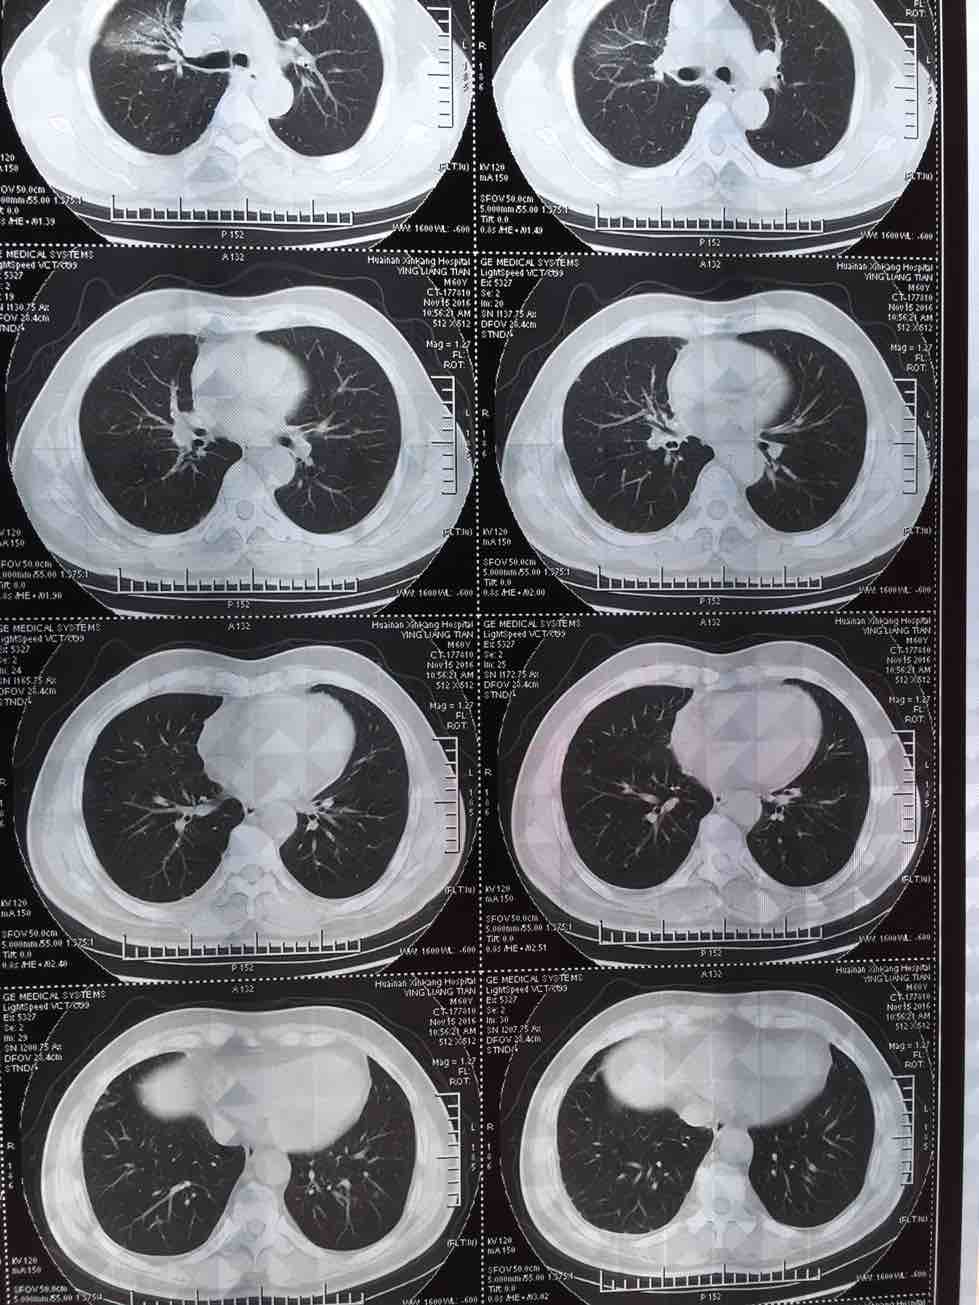

肺腺癌晚期治疗经验

我父亲今年一月份查出肺腺癌晚期伴两肺及腰椎骨盆转移,吉西他滨 顺铂两次,无效,后培美曲塞用了六次,最后一次今年7月25号出院,控制很好,期间主病兆放疗15次有所缩小,今年10月15号复查,两肺转移兆增多增大,紧接着做穿刺基因检测,结果野生型,顿时绝望,盲吃易瑞莎一个月,老天爷眷顾有效,病兆明显缩小或消失!!